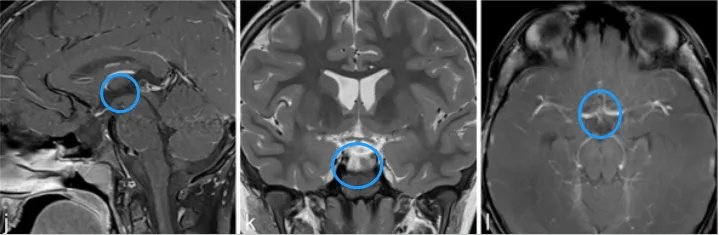

j、k、l图显示,肿瘤得到全切